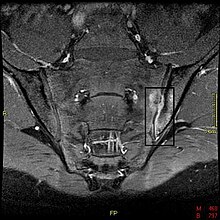

MRT bei Spondylitis der linken Kreuzdarmbeinfuge

In Röntgenbildern sind viele der Veränderungen des Bewegungsapparats sichtbar. Als Erstes kommt es normalerweise zu einer Sakroiliitis der Kreuzdarmbeingelenkfuge. Diese ist im Frühstadium des Morbus Bechterew auch der erste sichere Beleg zur Diagnose.

In späteren Stadien kann es zu Knochenspangen zwischen benachbarten Wirbeln, Spondylarthritis und Verknöcherungen des Wirbelkörperbandapparates kommen.Die Verknöcherung der Wirbelsäule ist auf Röntgenbildern gut zu erkennen und wird wegen ihrer markanten Form auch als Bambuswirbelsäule bezeichnet.

Im MRT (in der T2-Wichtung) ist eine Sakroiliitis schon Jahre eher erkennbar als im Röntgenbild.